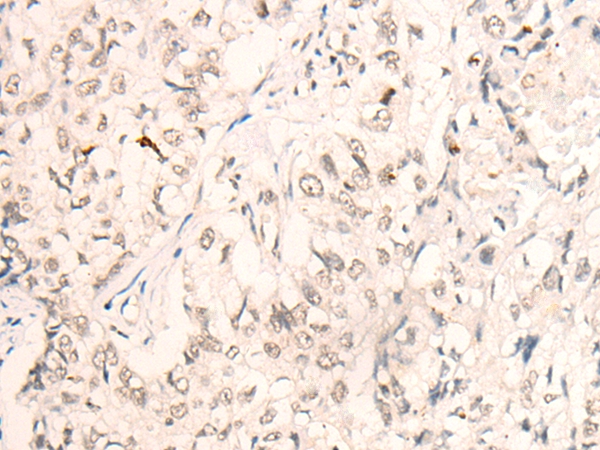

分类: 科研抗体货号: P43528别名: Speckle-type POZ protein (HIB homolog 1) (Roadkill homolog 1)应用: WB,IHC反应种属: Human,Mouse,Rat